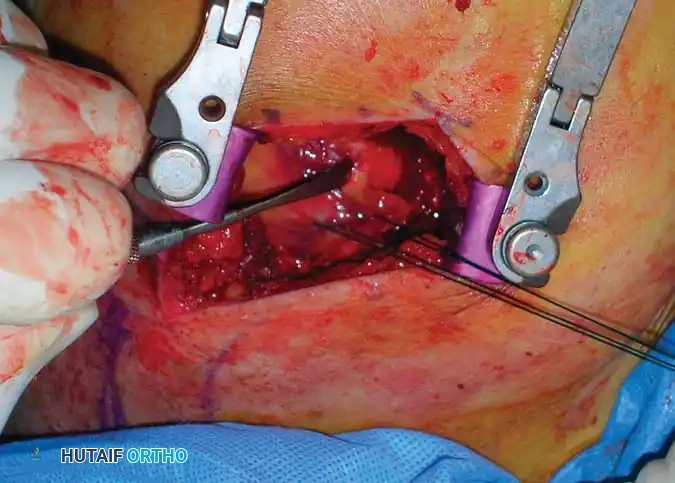

Glenoid Rim Fractures:

Fractures of the anterior or posterior glenoid rim associated with traumatic glenohumeral dislocations are likely more common than historically recognized. - Surgical Indication: If a glenoid rim fracture involves greater than 25% (one-fourth) of the articulating surface, primary open reduction and internal fixation are required to prevent recurrent instability, subluxation, or accelerated post-traumatic arthropathy.

Fig. 54-7 A, Fracture of anterior glenoid rim usually is produced by medially directed blow to humeral head. B, Large anterior glenoid rim fracture with associated posterior Hill-Sachs lesion. C and D, Open reduction and internal fi xation of glenoid rim fracture with single screw.